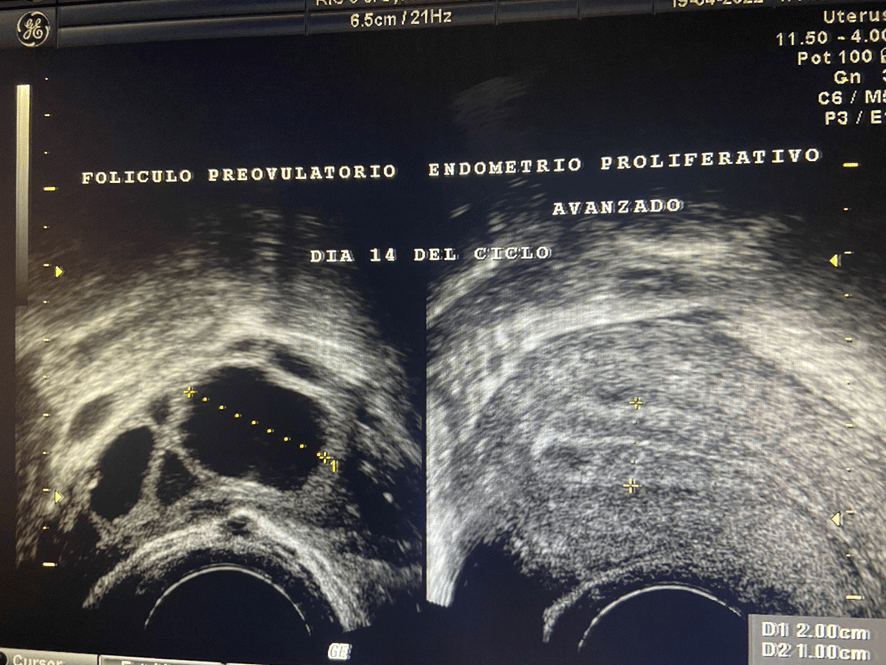

Una vez que el folículo maduro se ha roto -ha estallado- y se ha expulsado el óvulo que contenía (ovulación) la capsula del folículo adquiere un aspecto rugoso, grueso e irregular al que llamamos “cuerpo lúteo”. En su interior, frecuentemente, se produce un acúmulo de sangre por lo que también se le conoce como cuerpo lúteo hemorrágico.

Además de estrógenos, este cuerpo lúteo empieza a segregar una hormona llamada Progesterona; la cual, es la causante de que el endometrio- que antes de la ovulación era proliferativo y con sus tres capas bien definidas- se transforme en un endometrio grueso, espeso e irregular. Se le conoce como “endometrio secretor”.

Sumando los 14 días que suele durar la fase folicular o proliferativa a los otros 14 que dura la fase lútea, luteínica o secretora, nos dan los 28 días que suele durar el ciclo menstrual.